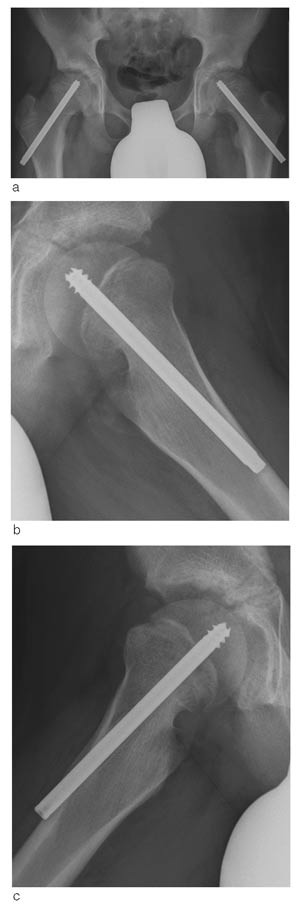

Vi fikk i 1992 spesialkonstruert en skrue som en modifisert Olmed-skrue (De Puy) og har siden da brukt denne rutinemessig ved epiphysiolysis capitis femoris. Målet var at skruen skulle kunne tillate fortsatt vekst i collum. Skruen har kortere gjengesegment enn vanlig Olmed-skrue som brukes til fractura colli femoris, for at hele gjengesegmentet kun skal stå i epifysen. Skruen er derfor glatt over vekstskiven, slik at den kan tillate fortsatt vekst i collum.

Det har tidligere vært til dels store problemer med å fjerne skruen (13, 14). For å redusere problemer med fjerning, er gjengene skjærende begge veier (fig 1, fig 2). Vi har med denne studien ønsket å kartlegge eventuelle problemer i tilknytning til operasjonsmetode både ved innsetting og ved fjerning av skruen, hvorvidt en skrue er tilstrekkelig i forhold til ev. ytterligere glidning og om det fortsatt skjer vekst i fysen. Videre har vi undersøkt forekomst av caputnekrose og kondrolyse og klinisk resultat ved oppfølging.

For å se på hvorvidt det skjer en fortsatt lengdevekst i collum med denne fiksasjonen, har vi målt endring i distale skrueendes protrusjon ved laterale cortex, artikulotrokantær avstand samt collumlengde ved operasjon og ved oppfølging.

Vi har målt distale skrueendes protrusjon ved laterale cortex i ti hofter. Gjennomsnittlig er den redusert med 0,53 cm per år (fig 3). Dette kan kun delvis forklares med økt bredde av femur ved økt vekst. Femurs bredde ved skruens distale ende har vi målt i seks hofter og gjennomsnittlig har femurs bredde ved laterale cortex økt med 0,17 cm per år.